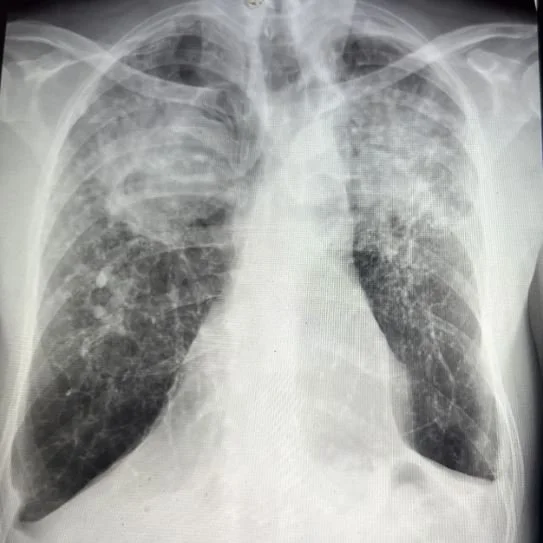

A 64 y.o. male from Mexico comes to the ED with shortness of breath.

Hint: He lived in the Trans-Mexico Volcanic belt and had bee a stone cutter for 40 years

Our patient had progressive massive pulmonary fibrosis (PMF)   from silicosis.  He had worked in a quarry in central Mexico  which is a known volcanic area containing tuff (volcanic ash hardened into rock).  In contrast to limestone which has little silica,  it is predominantly silica.  This stone,  called Cantara stone,  is used in construction throughout Mexico .

In progressive massive fibrosis small nodules form as a reaction to inhaled silica dust because the lungs cannot clear the tiny particles and macrophages try to wall them off. These small nodules coalesce into large dense masses of scar which typically appear in the upper lobes.  Fibrosis is divided into three main stage::acute is defined as occurring after weeks of exposure, accelerated occurs after 4-10 years of exposure and chronic progressive massive fibrosis (PMF).  occurs after more than ten years of exposure.   It is important to distinguish PMF from lung cancer which also has an upper lobe predilection because there is higher exposure to inhaled carcinogens in the upper lobes.  Lung cancer, however,  appears T2 hyperintense where PMF is hypointense compared to skeletal muscle.